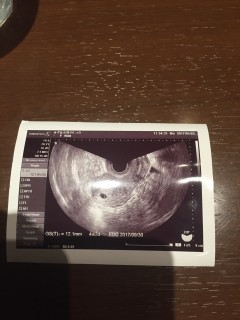

胎嚢10.8mm。 下腹部痛があるたまゆっくり休息しております。

胎嚢のみ確認できました。 前回生理開始日から6週だと思っていたら「現在5週です」との事。 1週間前の診察では影も形も見えず、子宮外妊娠かも…と思っていたので安心しました。

胎嚢(約9mm)確認できました。 現在5週0日目☆ 先生から非常に順調ですと言われて嬉しかったです。スクスク育ってほしいです!

生理遅れて6日、自宅にて検査薬したところ終了線出る前にくっきり陽性! 生理遅れて8日目に病院へ。 胎嚢確認!5w0dくらいだね、と言われました!